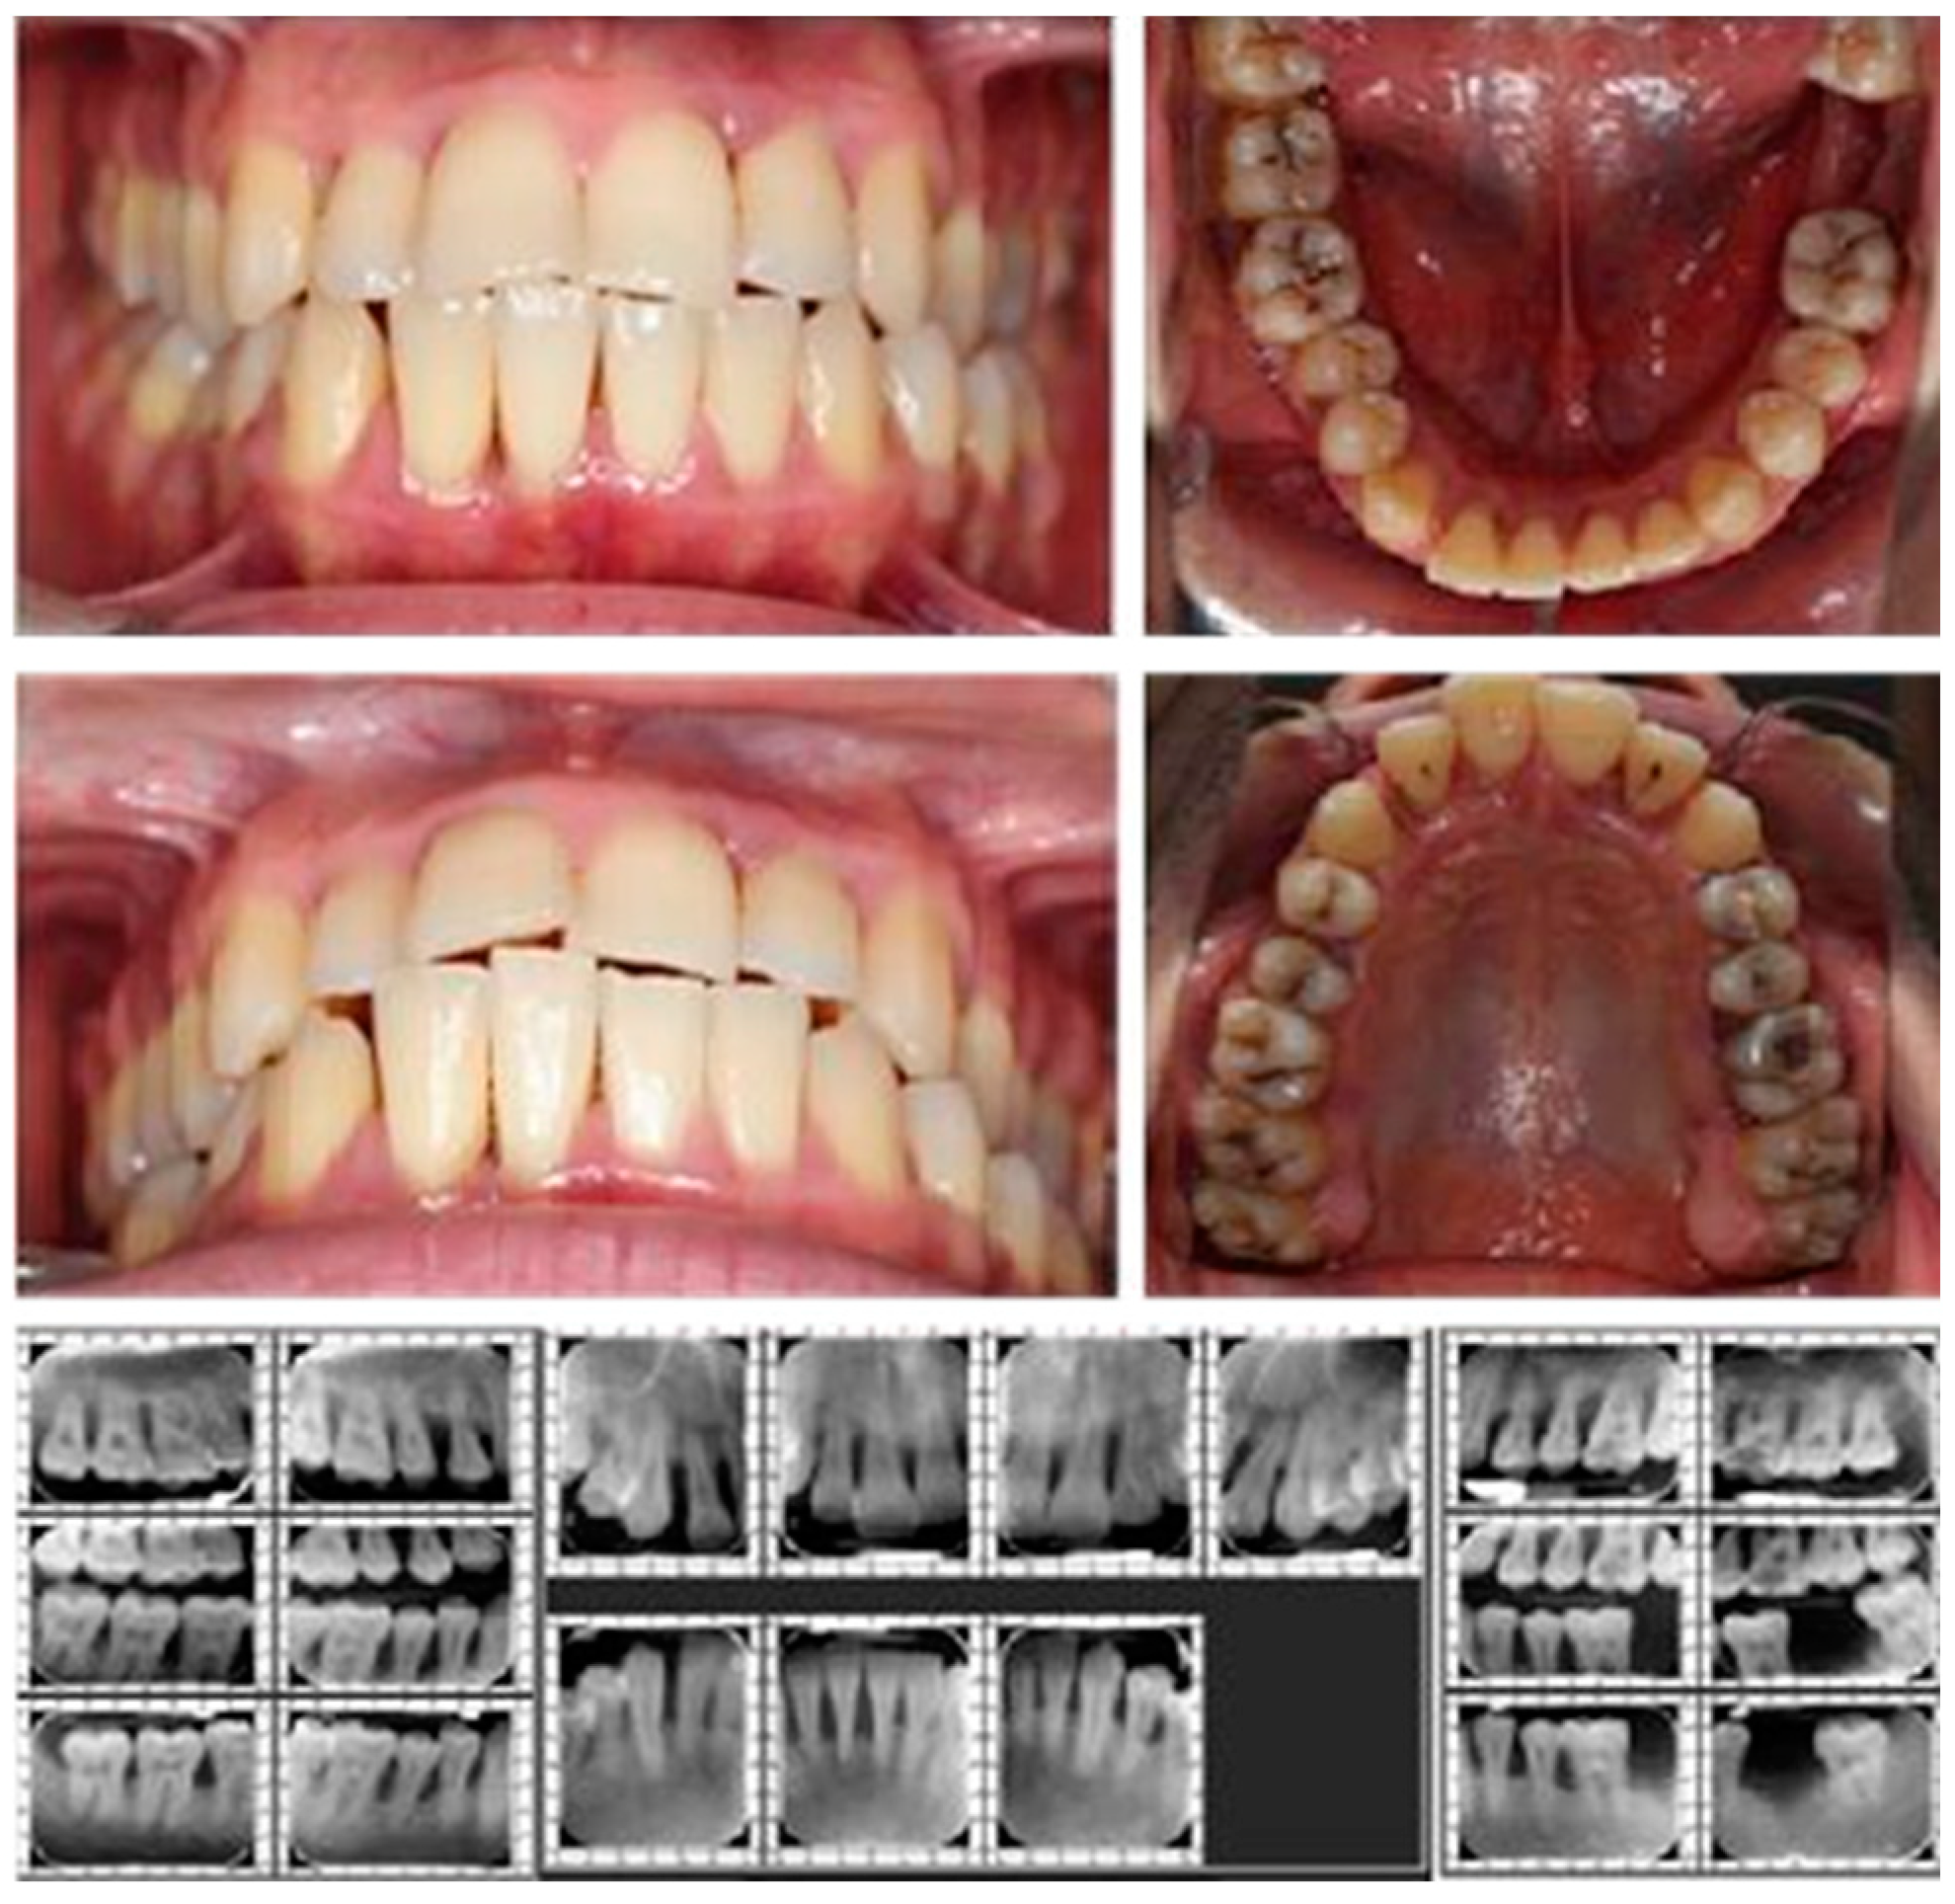

Case 1 was a 22-year-old male (Figure 1), without of known illnesses or systemic risk factors such as diabetes or hematological disorders, non-smoker, and not under any medication regimen.

Figure 1.

Case 1 - Clinical and radiological aspects.

From the routine medical analyses conducted, a deficiency of vitamin D was observed, without recommended treatment. The initial visit was prompted by concerns about tooth mobility that had developed over the past 2 years, poor aesthetic appearance of the gums and tooth misalignment. The initial examination revealed deep probing pocket depths, tooth mobility, bleeding upon probing, gum recession, and signs of gingival inflammation (Figure 1 and Figure 2).

The plaque index score registered were 76%, radiographic bone loss 55% (more than half of the tooth's root) The bleeding upon probing index (BOP) measured at 45%. The probing depth (PD) was 8 mm for both maxillary incisors and 7 mm for the mandibular first molars and premolars. Tooth mobility, assessed using the Miller Classification, was categorized as class 1 for both maxillary and mandibular incisors, and class 2 for the left mandibular lateral incisor (Figure 2).

Among the local predisposing factors contributing to periodontal disease, observations included dental malposition of the maxillary and mandibular central and lateral incisors, deep bite malocclusion, and the presence of deep and advanced carious lesions in both maxillary and mandibular molars and premolars. The diagnosis was periodontitis stage III, grade C. Stage III of periodontitis in this case, was defined based on the severity and complexity of management. The grade of periodontitis was estimated with direct or indirect evidence of % bone loss/age > 1.0 and destruction exceeding biofilm deposits (suggestive of rapid progression and early onset disease) [27,28]. The orthodontic diagnostic was class II, division 1 malocclusion (Angle classification).